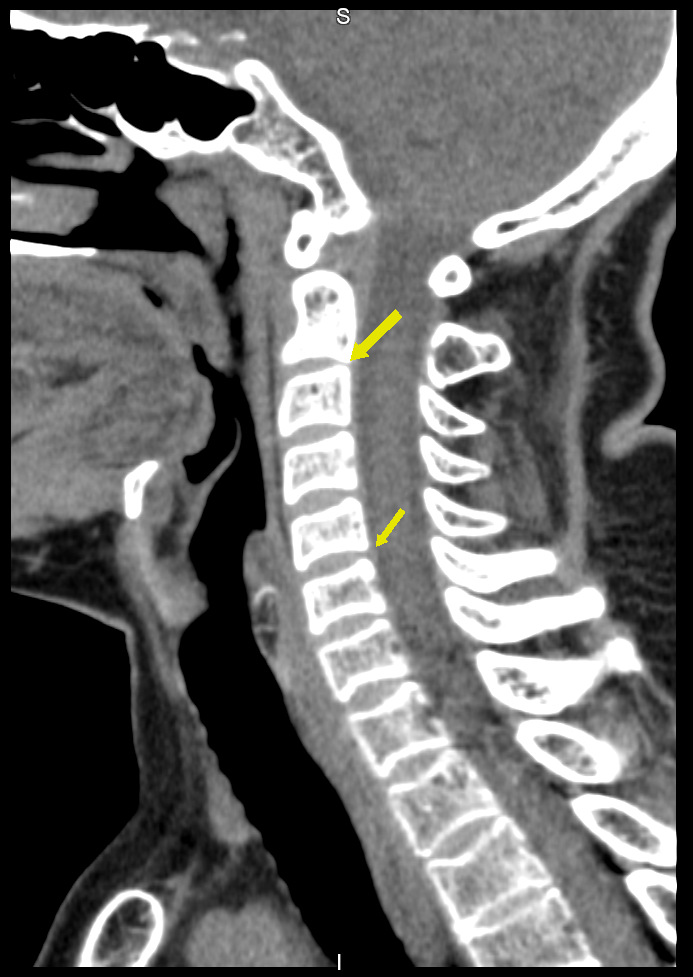

A tomografia computadorizada de coluna é um exame de imagem de alta qualidade e nitidez, que proporciona a identificação de várias patologias que atingem a área da coluna vertebral, como espondilose (artrose na coluna), estenose vertebral (aperto na coluna), espondilolistese (deslizamentos vertebrais), traumas e outros. A ressonância apresenta sensibilidade maior para detectar hérnias. Contudo, nos casos de trauma, a tomografia computadorizada é um excelente método de imagem.